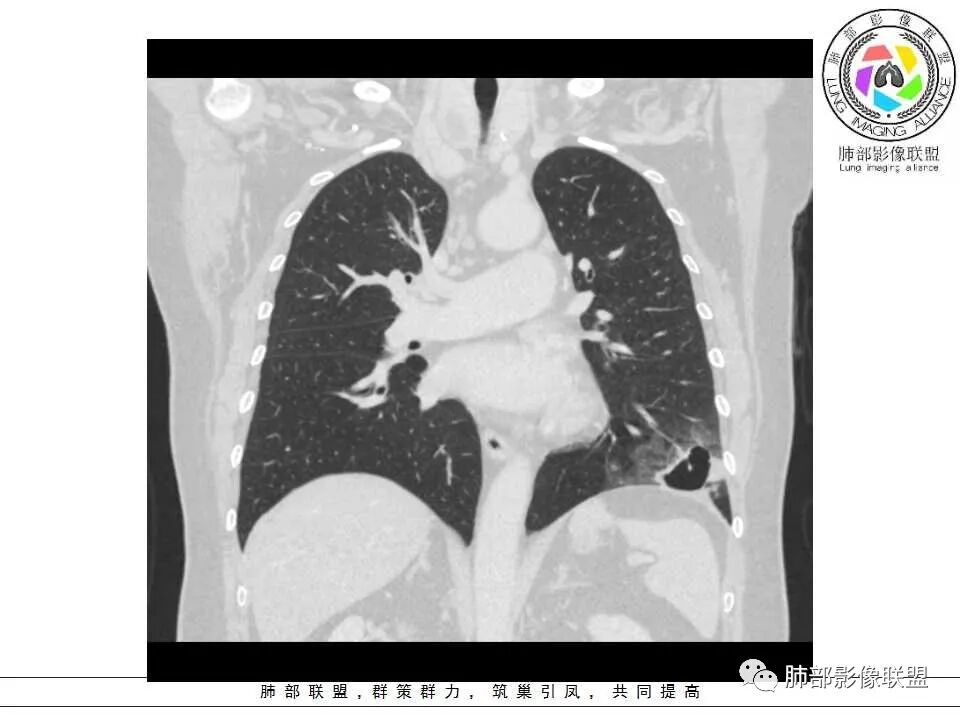

病灶分两部分

周围大片GGO

中央囊实性病变

3、灶周环以大范围磨玻璃影,非常均匀,没有重力分布趋势,分叶状,边界隐约可变。

4、冠状位部分层面可见支气管在囊腔边缘截断。

本例囊腔性病灶尽管腔壁稍显僵硬,壁结节凸显,但女性患者,灶周明显磨玻璃晕,都强烈提示为囊腔性腺癌。